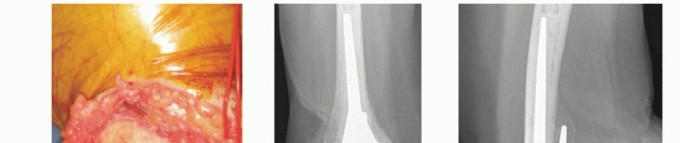

Identify the olecranon fossa (if any part of it still exists). This landmark is the seating point for the base of the anterior flange of the Coonrad-Morrey humeral component (TECH FIG 4A). If the olecranon fossa is not present owing to a greater degree of comminution, an extended flange humeral component can be used.

Release the anterior capsule and any soft tissue from the anterior surface of the distal humerus. This provides a site for the anterior humeral bone graft.

The posterior flat surface of the humerus is identified because this plane approximates the axis of rotation of the distal humerus (TECH FIG 4B). Humeral canal preparation is completed with the canal broaches

provided with the implant system being used.

The ulnar canal preparation commences with removal of the tip of the olecranon. The intramedullary canal is entered at the base of the coronoid (TECH FIG 4C,D).

The entry point is enlarged toward the coronoid with a burr to allow easier component insertion without cortical abutment, which leads to malalignment (TECH FIG 4E).

During intramedullary preparation, the broaches must parallel the subcutaneous border of the ulna. This ensures that the track of insertion of the ulna parallels the intramedullary canal. This may require removal of bone from the greater sigmoid notch of the ulna.

The tip of the coronoid is removed to avoid impingement during terminal flexion (TECH FIG 4F,G).

The radial head does not need to be resected if there is no disease of the proximal radioulnar joint (TECH FIG 4H).

TECH FIG 4 • A. The humeral component entry point, the apex of the olecranon fossa, is identified, and humeral canal preparation is commenced by opening the canal with a bone nibbler or burr. (continued)

TECH FIG 4 • (continued) B. The posterior flat surface of the humeral shaft is identified and the component is aligned. C,D. Ulnar canal preparation is commenced by opening the canal at the base of the coronoid process with a drill or burr. E. The trajectory of the ulnar component (black ring) is prepared by rasping the entry track posteriorly into the ulna with a rasp or bone nibbler (gray crescent). F,G. The tip of the coronoid should be resected sufficiently to prevent abutment on the humeral flange during full flexion. Also shown are the resections of the olecranon and the entry point for the ulnar stem insertion. H. The partially resected radial head is used as a bone graft for incorporation behind the humeral flange.